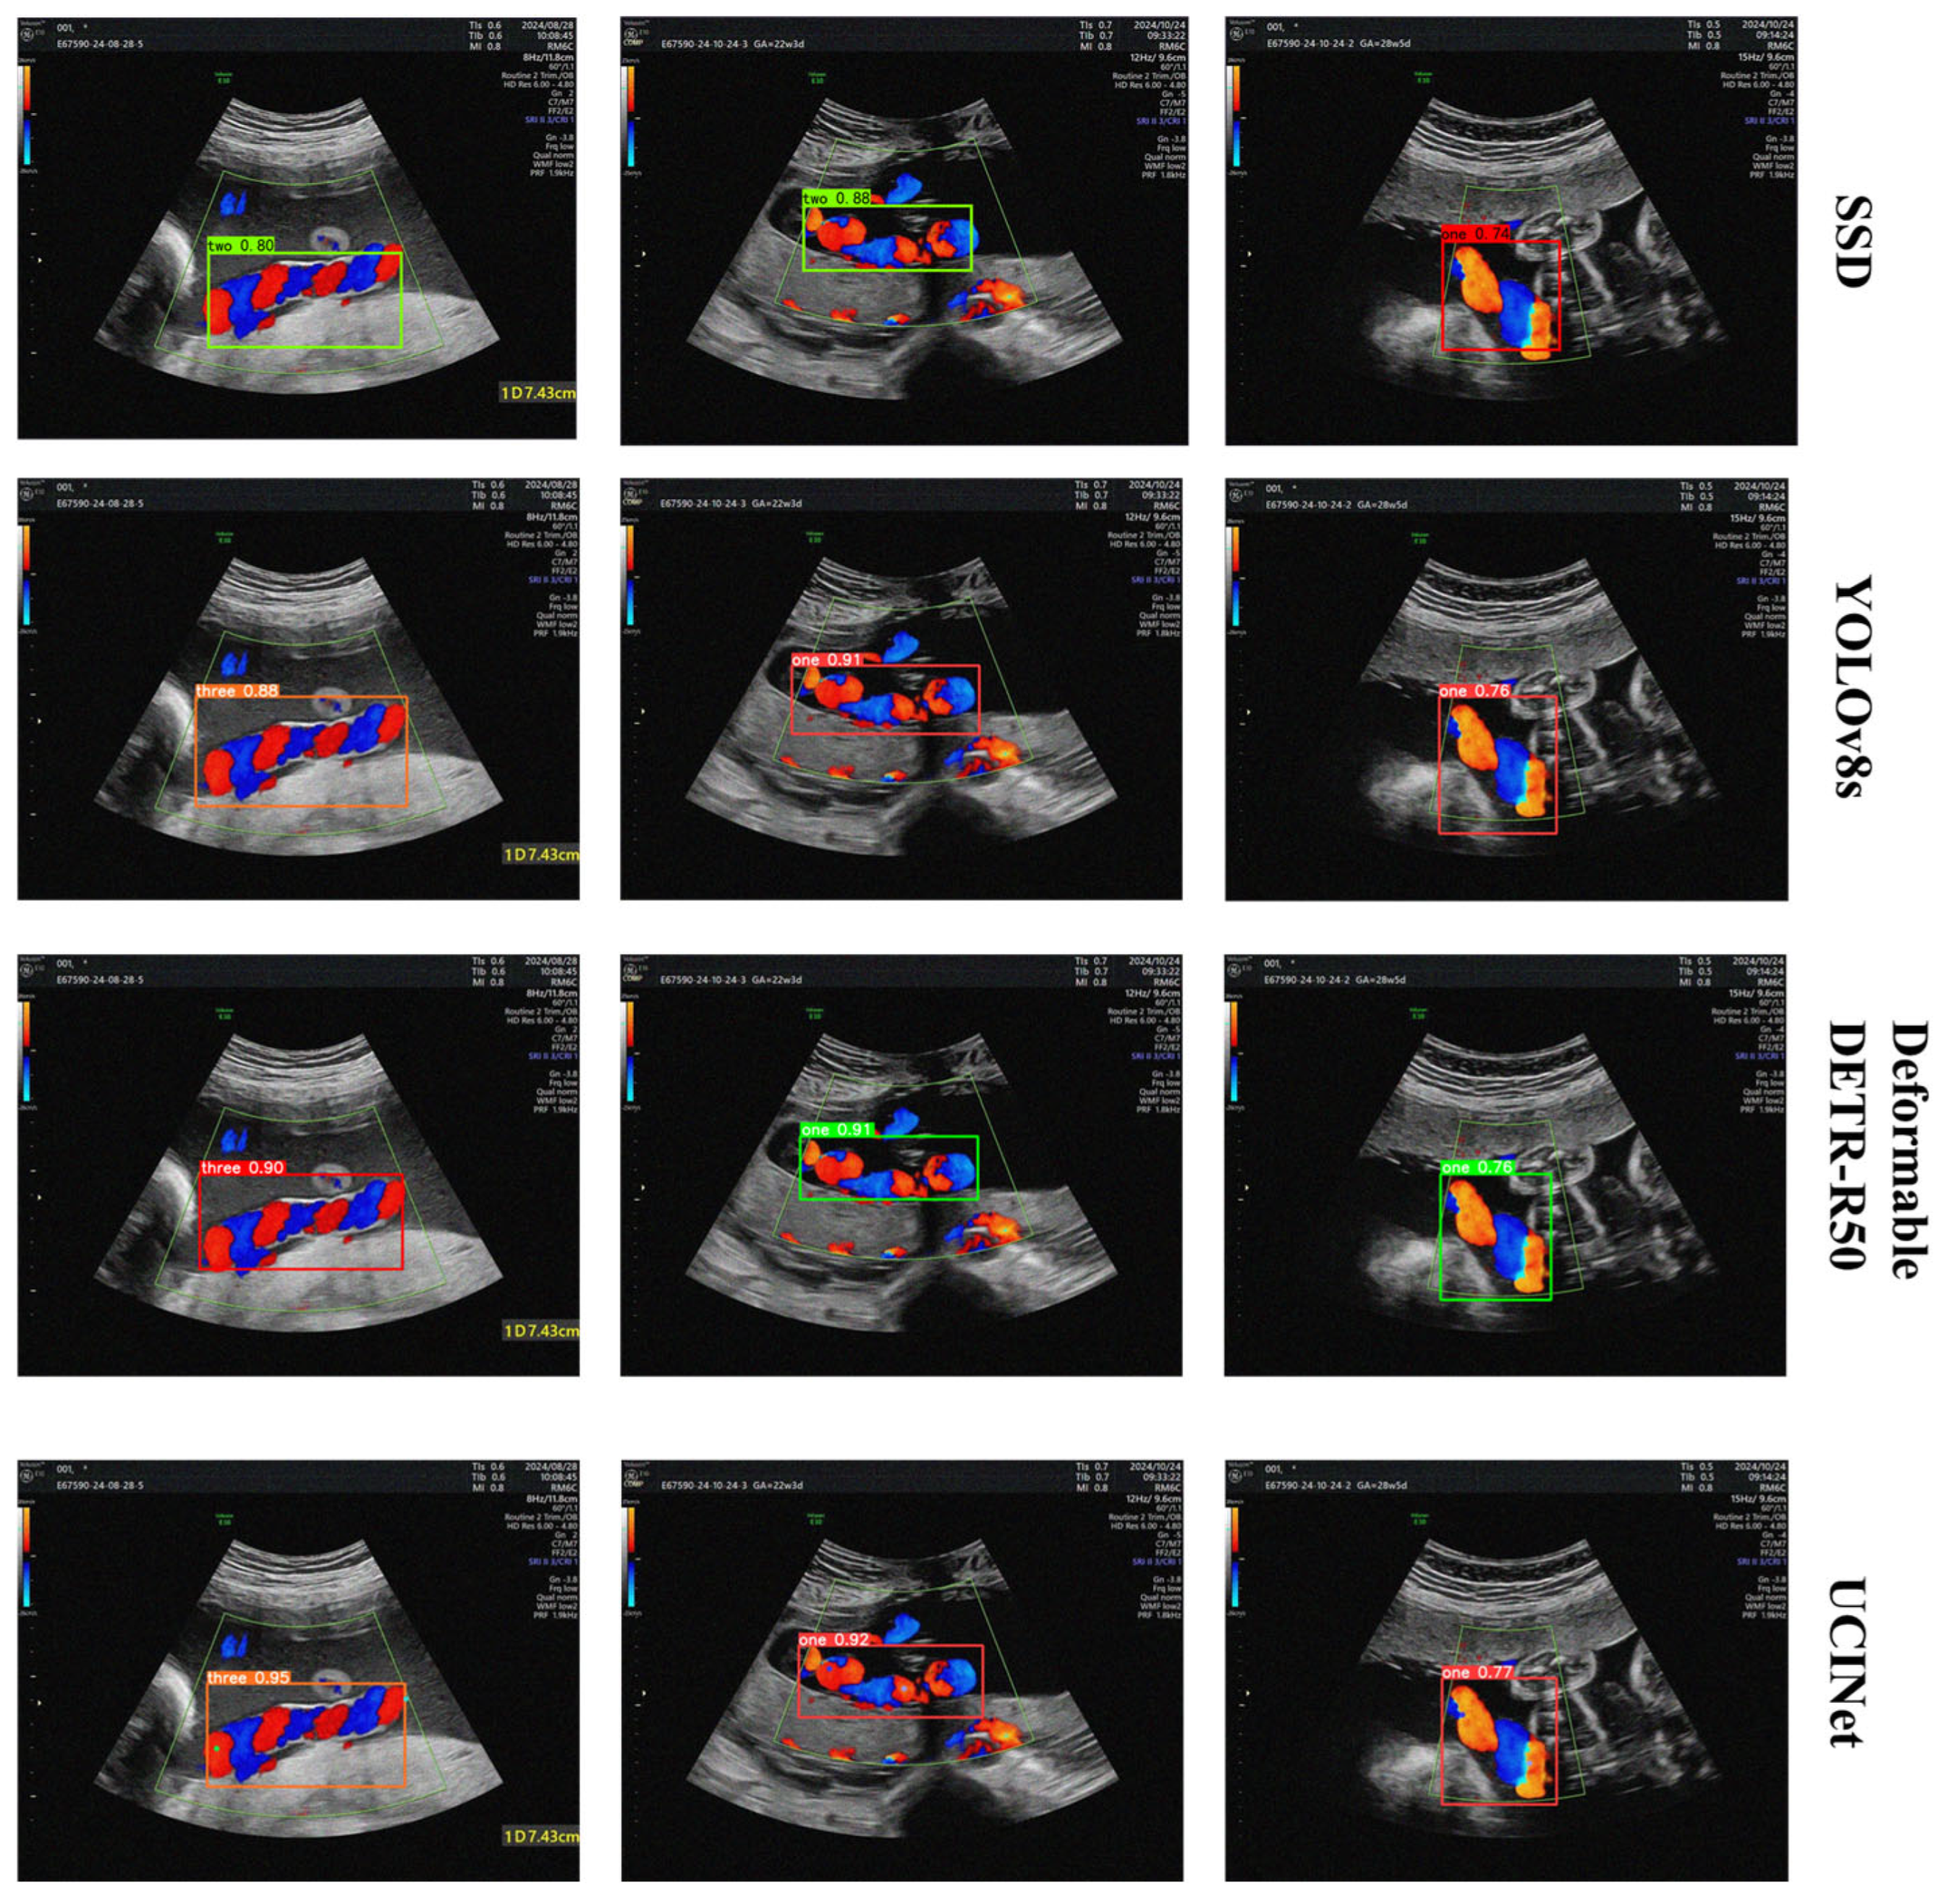

In the object detection task, comprehensive comparisons were made between UCINet and several mainstream models, including SSD [33], Faster R-CNN [34], YOLOv5s, YOLOv8s, YOLOv11s [35], and the transformer-based Deformable DETR-R50 [36]. The experiments were conducted on the UCI and public Ear210 datasets to thoroughly evaluate detection accuracy, model complexity, and inference efficiency across different scenarios.

On the UCI dataset, UCINet demonstrated consistent superiority across multiple metrics. As summarized in Table 1, UCINet achieves a mAP@50 of 84.2% and a mAP@50–95 of 61.5%, outperforming all CNN- and Transformer-based baselines. For instance, UCINet surpasses SSD with improvements of 15.3 percentage points in mAP@50 and 18.3% in mAP@50–95, while requiring only 38% of its parameters and achieving more than twice the inference speed. Compared with Faster R-CNN, UCINet reduces the parameter count by 32.2 million, improves mAP@50–95 by 12.6%, and achieves a 5.7-fold increase in FPS, confirming its strong real-time capability.

The YOLO family baselines further highlight UCINet’s efficiency. Despite having a model size comparable to YOLOv5s and YOLOv11s, UCINet achieves gains of 9.1% and 2.7% in mAP@50, respectively, while maintaining higher inference speed. Even against Deformable DETR-R50, which represents a more advanced transformer-based detector, UCINet provides improvements of 1.2% and 1.5% mAP@50–95 improvements, while reducing parameters from 40.5 M to 9.2 M and boosting FPS from 22 to 109. These results indicate that UCINet achieves more efficient feature representation and superior detection accuracy under clinical imaging conditions.

On the Ear210 dataset, UCINet further validated its generalization ability. As shown in Table 2, UCINet outperforms SSD and Faster R-CNN by 21.0% and 8.8% in mAP@50, and by 22.1% and 11.0% in mAP@50–95, respectively. Compared with YOLOv11s, UCINet achieves additional improvements of 1.1% in mAP@50 and 2.5% in mAP@50–95. The visualization results in Figure 7 further confirm that UCINet provides more accurate localization of the umbilical cord region with tighter bounding boxes and higher confidence, whereas SSD frequently suffers from false positives. In summary, UCINet effectively balances detection accuracy and inference efficiency, maintaining a lightweight architecture while outperforming CNN- and Transformer-based baselines on both private and public datasets. These results confirm the model’s superior generalization ability and highlight its potential for real-world deployment in clinical ultrasound analysis. As illustrated in Figure 8, further demonstrating the effectiveness of the proposed method.

Figure 8. Visualization of object detection results of UCINet and other methods on the UCI dataset.